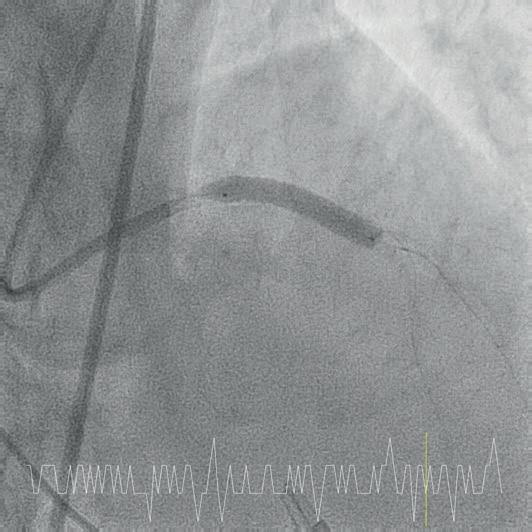

Intracoronary imaging

Among the major changes to the latest version of the guidelines is a new emphasis intravascular imaging. When performing revascularisation via PCI, intracoronary imaging—in the form of intravascular ultrasound (IVUS) or optical coherence tomography (OCT) —is deemed as being helpful to guide interventions and enhance results, especially in complex scenarios including left main disease, bifurcations, or long lesions.

on a multitude of randomised controlled trials showing consistent substantial clinical benefit,” said Lorenz Räber (Bern University Hospital, Bern, Switzerland), highlighting the importance of this new recommendation to Cardiovascular News. “Europe is lagging behind, as many believe angio is enough, so the upgrade is expected to fuel the use of imaging for complex lesions. Currently, there is no other technical refinement of PCI that reportedly improves clinical outcomes to the degree observed with intracoronary imaging.”

“Meta-analysis of randomised clinical trials had already shown that intracoronary image guidance of PCI improves patient outcomes and saves lives,” said Javier Escaned (Hospital Clinico San Carlos, Madrid, Spain). “But the IA recommendation for IVUS in the updated ESC guidelines is crucial, as it reflects expert consensus based on a definite body of evidence supporting the positive impact of IVUS, specifically for patients with anatomically complex lesions treated with PCI.”